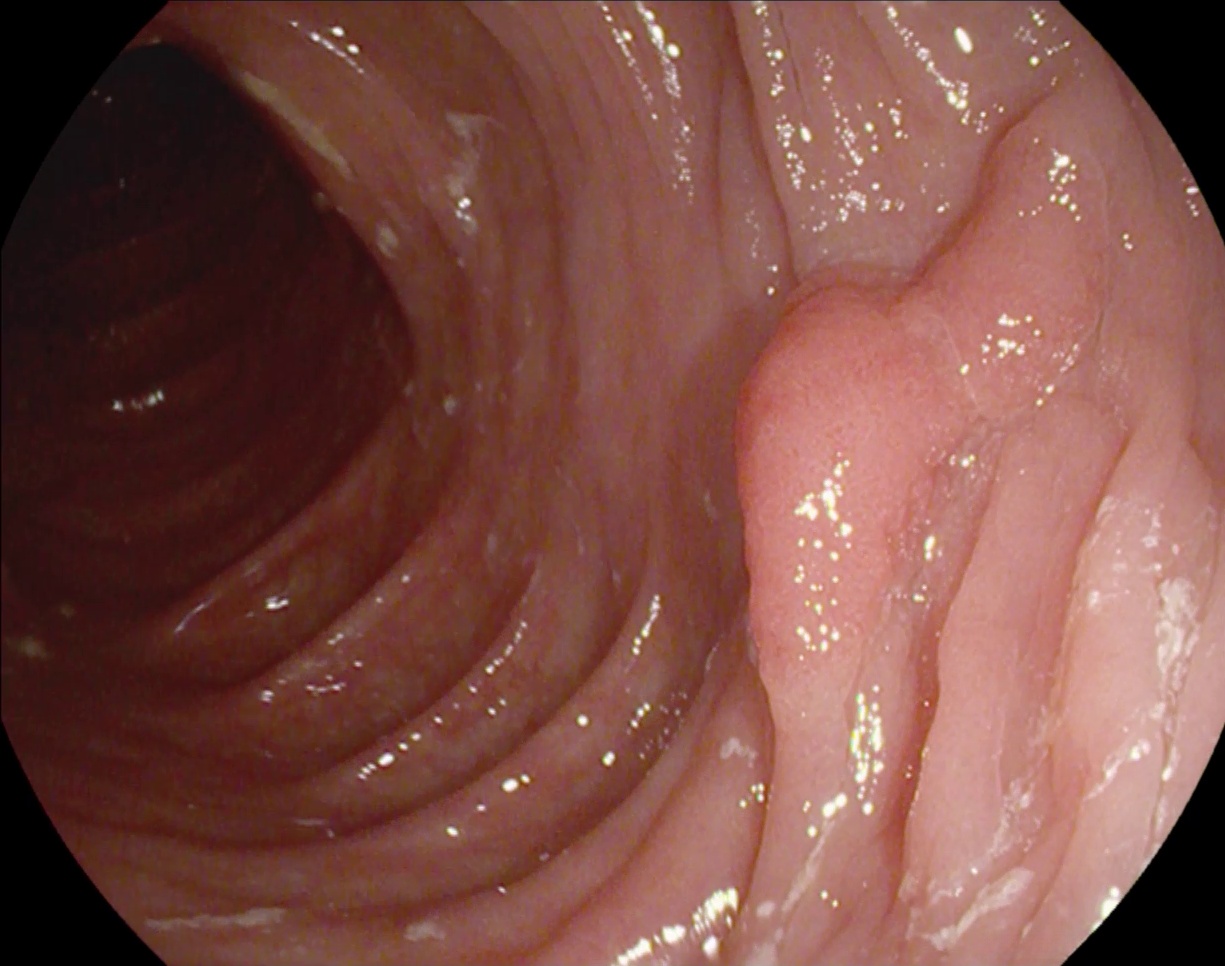

1、ClinicDB : 这是一个开放的数据集,致力于提供高质量的结肠镜图像以及相应的结肠息肉标注. 该数据集旨在促进计算机辅助诊断(CAD)系统的研发,从而在临床环境中提高结肠息肉检测与分类的效率. 数据集中包含大量高清晰度的医学影像,并结合多模态标注信息,为相关领域的研究提供丰富的学习素材. 通过系统化的数据积累,ClinicDB不仅能够显著提升诊断准确性,还能为临床实践提供科学依据.

处理好后的COCO格式的数据集图像的总数为612张,类型标签为病灶区域。